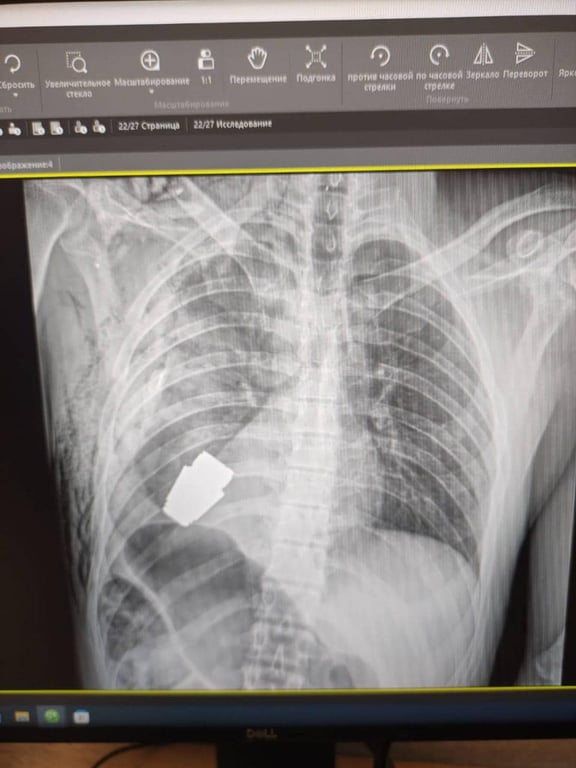

Нерозірвана граната застрягла біля серця: неймовірна історія порятунку пораненого воїна ЗСУ

Військові лікарі провели операцію з видалення гранати ВОГ з тіла військовослужбовця. Операція проводилася у присутності двох саперів.

"Не кожне поранення в області серця є смертельним! Військові лікарі провели операцію з видалення гранати ВОГ, яка не розірвалася, з тіла військовослужбовця. Її було видалено у присутності двох саперів, які страхували безпеку медичного персоналу", — розповіла чиновниця.

За словами Маляр, операція проводилася одним з найдосвідченіших хірургів ЗСУ — Андрієм Вербою — без електрокоагуляції, оскільки граната могла детонувати у будь-який момент.

"Оперативне втручання пройшло успішно, а пораненого військовослужбовця було відправлено на подальшу реабілітацію та відновлення", — написала заступниця міністра.